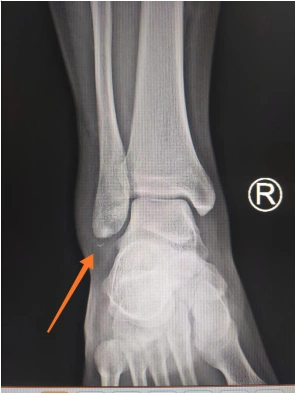

给小夏进行了仔细检查,检查结果为右外踝骨折,右外踝关节侧副韧带断裂